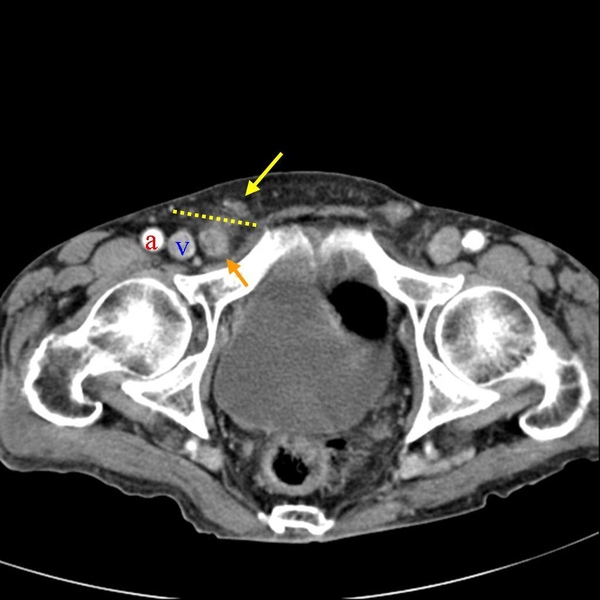

下面這張圖有點兒複雜,先看到黃色虛線,這大約是腹股溝韌帶(Inguinal ligament)的所在。在腹股溝韌帶上方,可以見到精索(黃色箭頭),這個位置也是方才提到腹股溝疝氣的位置。在腹股溝韌帶(Inguinal ligament)下方,正常時候只可見到股動脈(Feomral artery)、股靜脈(Femoral vein),圖中橘色箭頭多出來的部分便是股疝氣。

下圖可以見到股靜脈內側,橘色箭頭處,凸出的一塊,這便是股疝氣。這個位置周圍被韌帶及骨頭包圍,空間有限,所以股疝氣一般尺寸不會太大。卻也因為入口處狹窄堅固,便容易導致嵌頓。